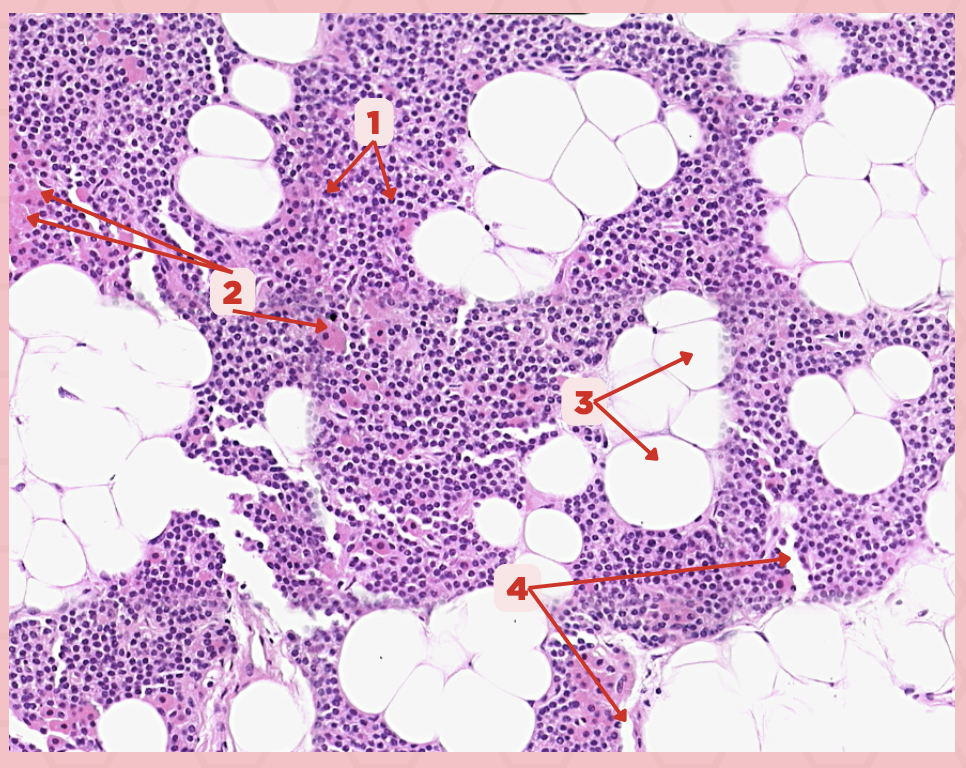

Parathyroid

Identify the specimen.

Chief Cells

Identify the specimen labeled as 1.

Oxyphil Cells

Identify the specimen labeled as 2.

Adipocytes

Identify the specimen labeled as 3.

Capillaries

Identify the specimen labeled as 4.

Newborns

Pointer #2 is hardly present in the parathyroid glands of _____.